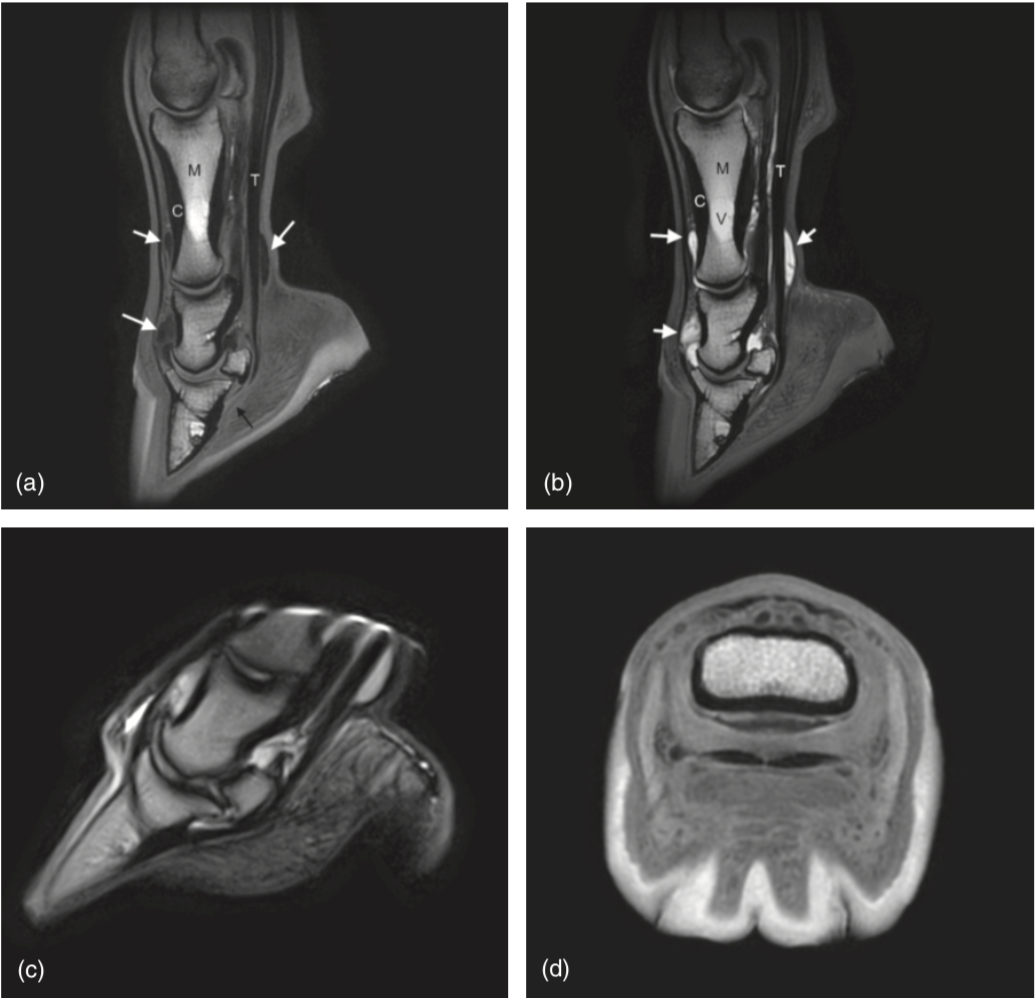

(Note hypointense fluid in DIP and NB - red arrows)

Appearance of fat and fluid on T2-weighted images

On T2 - 2 things are white; fat and water

Trabecular bone and synovial fluid are both hyperintense. The easiest way to distinguish T1 and T2 images is to observe the signal intensity of fluid.

How to differentiate fluid from sclerosis

Need to look at multiple sequences

Fluid and sclerosis are indistinguishable on T1-weighted images. However fluid will have intermediate-high signal intensity on T2, STIR and PD images

PD and T2-weighted FSE sequences provide a definitive way to identify sclerosis, when compared with the T2* gradient-echo images as there is no overlap between the appearance of fluid and sclerosis on these sequences